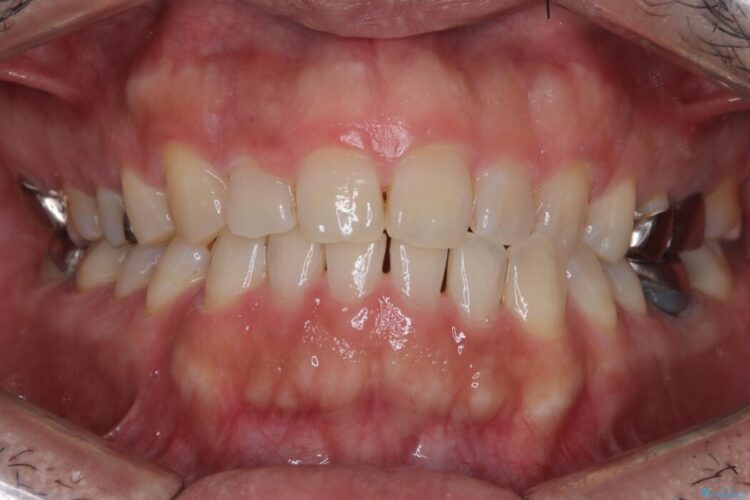

再根管治療とオールセラミックで前歯の気になる変色を解消

再根管治療とオールセラミックで前歯の気になる変色を解消 ビフォー 再根管治療とオールセラミックで前歯の気になる変色を解消 アフター

他院で神経を取った前歯が変色してきたとご相談にいらした患者様です。